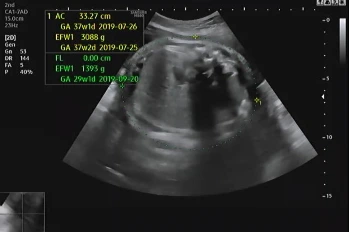

임신 39주 4일 차 병원에 내원해 초음파를 확인했다. 지난번에 이어 큰 이상이 없어 2주 뒤에 내원했는데 다행히 태아도 그동안 건강함을 알려주듯 초음파를 보는 내내 열심히 움직였다.

자궁경부의 길이는 지난번에 비해 얇아졌지만 여전히 아기는 골반에 위치하지 않고 위에서 놀고 있다고 했다. 자세를 잡은 지는 몇 주가 넘었지만 내려올 생각이 없이 열심히 놀기 바쁜 아기에게 얼른 내려오라고 이야기했는데 엄마의 말을 들어줄 생각이 없는 것 같다.